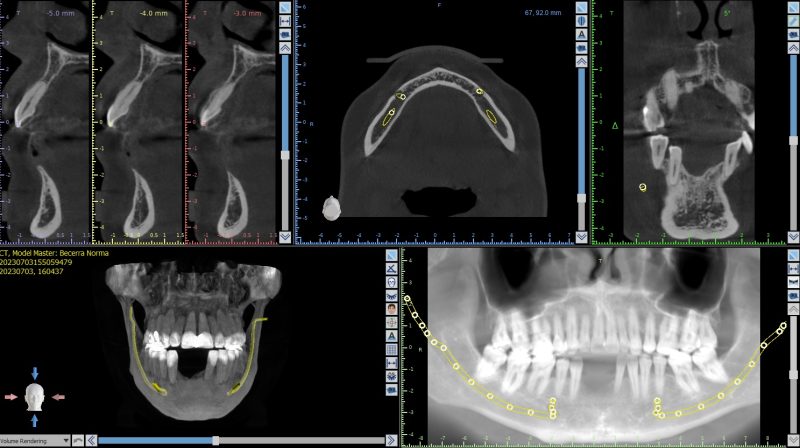

• New grad here….

Have a patient with implants placed at 3 &4 several years ago but didn’t have the funds to restore them until now. Obviously, the anterior one doesn’t look so great radiographically (no bleeding inflammation, etc clinically). Both feel solid and pass the mirror-tapping test.

Would you guys think #3 could still be restored?…

Read more

• I would remove them both and start over. The only way I’d restore 3 is if it was aware that it had less than 5 year prognosis. The issue was tissue thickness which was less than 2mm thick in all dimensions. I would just be honest with pt that their bone didn’t heal well and you’re concerned about long term prognosis. If they were hell bent I…